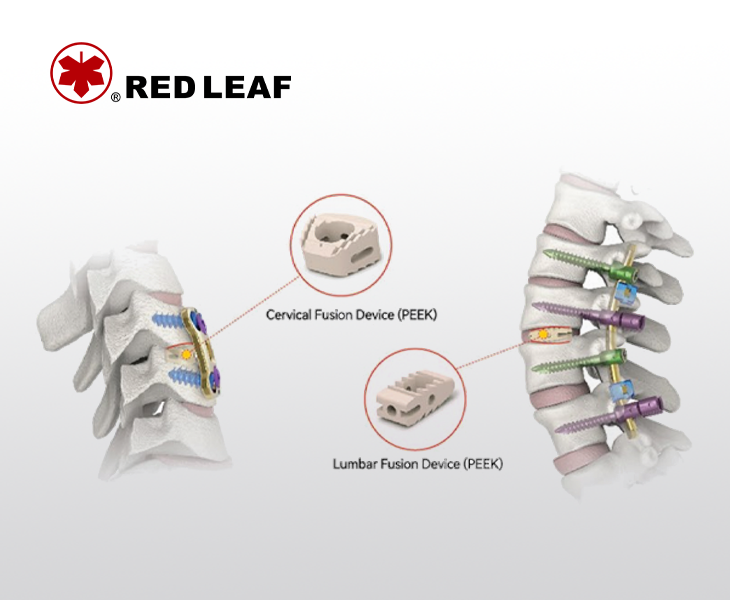

The lumbar and cervical fusion cage is made of Peek biomaterials, which have good biocompatibility

Stable, Visible, Reliable — PEEK Fusion System

Intervertebral fusion systems are popular in spinal surgery as they provide stable support for spinal fractures, maintain spinal sequence, and can be used to treat degenerative diseases, trauma, tumors, and other spinal disorders.PEEK material has excellent biocompatibility, corrosion resistance, and high elasticity, which is very similar to human bones and closer to the elasticity of bones. It can maintain long-term stability and bone fusion of the spine after surgery, and has good transparency without affecting postoperative monitoring and observation. It is highly favored by doctors and patients.

Spinal implants are medical devices made of biomaterials such as titanium alloys, PEEK, metals, and ceramics to treat and alleviate spinal diseases. They are commonly used in surgery for conditions such as scoliosis, spinal fractures, cervical spondylosis, and tumors.

Spinal implants are used in spinal surgery to fix and correct deformities. They consist of components such as connecting rods, pedicle screws, implantable plates, interbody fusion cages, and titanium cages, providing stability in the anatomical reconstruction of the human spinal surgery.

Spinal implant fixation surgery typically uses biocompatible implant material such as titanium alloys and PEEK (polyetheretherketone).

Spinal implant surgery involves implanting pedicle screws, connecting rods, plates, and other implants into the vertebral bodies to stabilize the spinal skeletal structure, correct deformities, and relieve nerve compression.